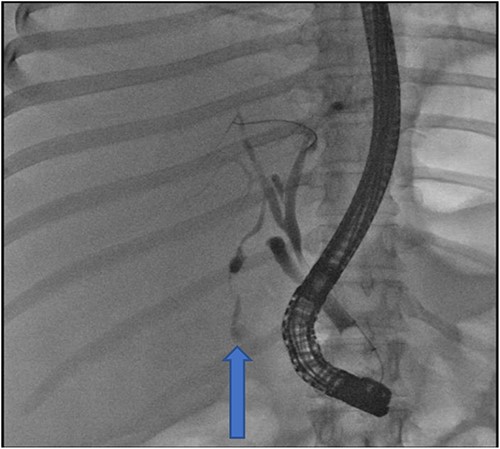

At our facility, ERCP was done. The bile duct was cannulated with 0.035 wire-guided sphincterotome. Cholangiogram showed normal caliber biliary tree with one filling defect in the distal CBD and contrast leak from duct of Luschka to the gall bladder bed (Fig. 1). There was no contrast leak from the cystic duct stump (Fig. 2A). Standard sphincterotomy was performed and a single mulberry stone was removed using stone retreival balloon and double pig tail biliary plastic stent was placed into the RHD and good bile flow was achieved post procedure (Fig. 2B).

(A) First fluoroscopic image shows evidence of no bile leak from cystic duct stump as indicated by the arrows; (B) second fluoroscopic image shows a stent placed into the RHD.